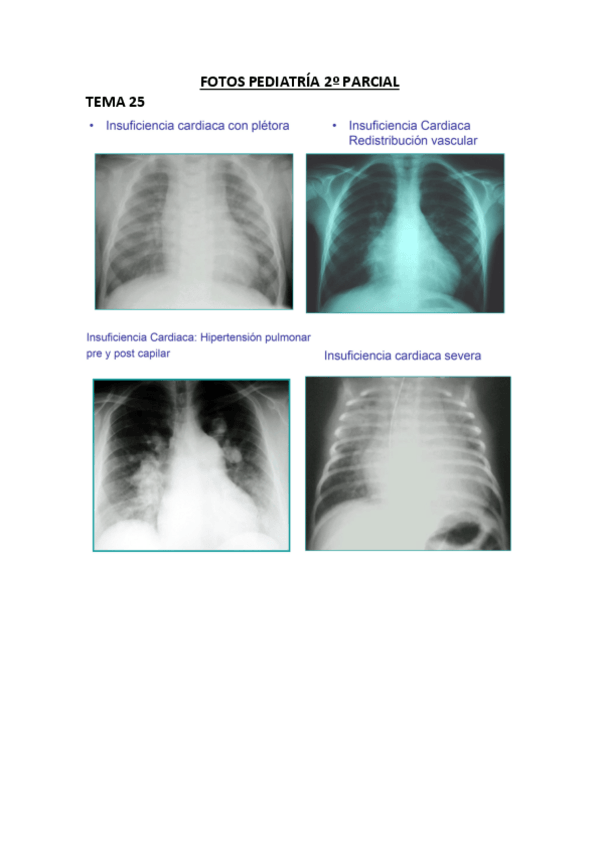

He publicado nuevos apuntes de 4º Pediatría: FOTOS-PEDIATRIA-2o-PARCIAL.pdf